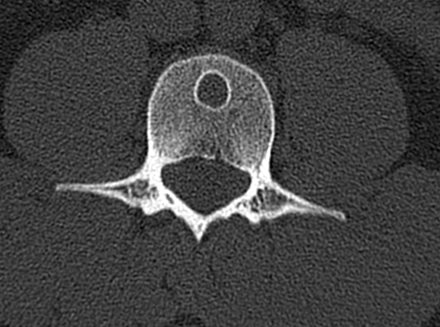

Для уточнения диагноза выполняют рентгенологическое исследование пораженного сегмента: рентгенографию бедренной кости, рентгенографию плечевой кости и т. д. На основании рентгенологической картины определяют фазу патологического процесса. В фазе остеолиза на снимке обнаруживается бесструктурное разрежение метафиза, соприкасающееся с зоной роста. В фазе отграничения на рентгенограммах видна полость с ячеистым рисунком, окруженная плотной стенкой и отделенная от зоны роста участком нормальной кости. В фазе восстановления на снимках выявляется участок уплотнения костной ткани или небольшая остаточная полость.

Различают две формы аневризмальных костных кист: центральную и эксцентрическую. В течении болезни выделяют такие же фазы, как и при солитарных кистах. Клинические проявления достигают максимума в фазе остеолиза, постепенно уменьшаются в фазе отграничения и исчезают в фазе восстановления. На рентгенограммах в фазе остеолиза выявляется бесструктурный очаг с внекостным и внутрикостным компонентом, при эксцентричных кистах внекостная часть по размеру превышает внутрикостную. Надкостница всегда сохранена. В фазе отграничения между внутрикостной зоной и здоровой костью образуется участок склероза, а внекостная зона уплотняется и уменьшается в размере. В фазе восстановления на рентгенограммах обнаруживается участок гиперостоза или остаточная полость.